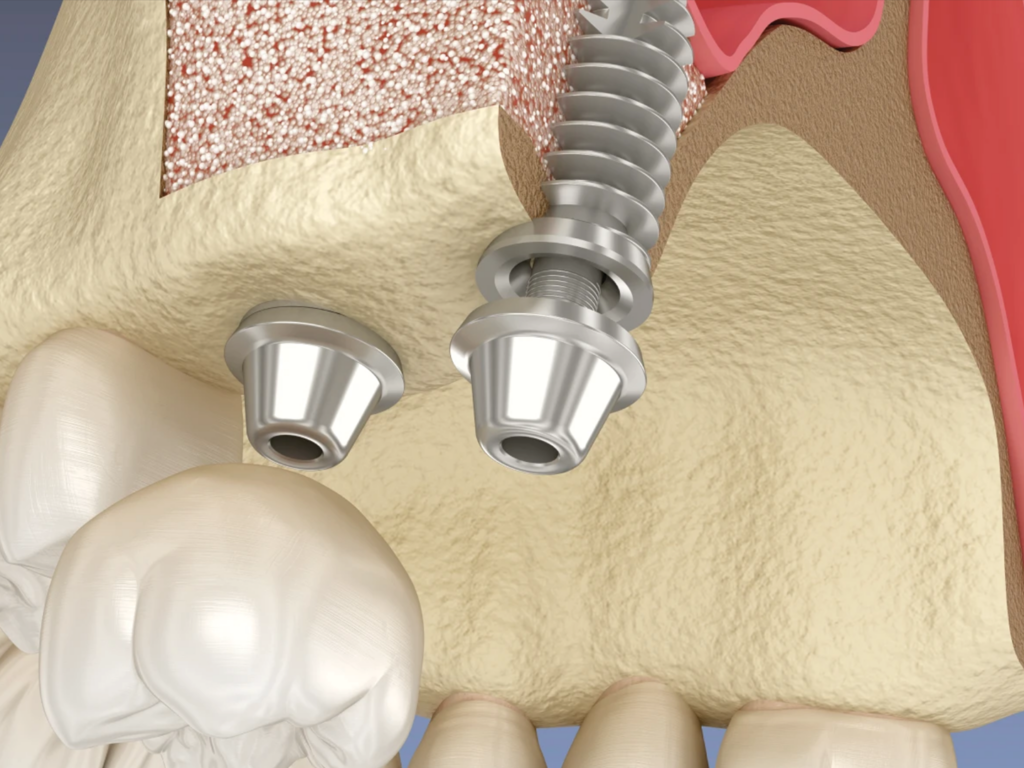

Greffe osseuse / comblement osseux

Reconstruction de l’os quand il est insuffisant, pour stabiliser la zone et/ou préparer un futur implant.

Sinus lift

Augmentation osseuse au niveau du sinus (mâchoire supérieure) permettant la pose d’implants dans de bonnes conditions.

- Un projet d’implant avec manque d’os (greffe / sinus lift)

Possibilité de préparation pré-implantaire (greffe / sinus lift) selon indication

-Si l’os est insuffisant, on peut le reconstruire ou l’augmenter afin de sécuriser et rendre possible la pose d’implant dans de bonnes conditions.

Greffe osseuse / sinus lift : est-ce dangereux ?

-Ce sont des techniques courantes quand l’os est insuffisant. Elles servent à sécuriser le traitement et rendre possible l’implant dans de bonnes conditions. On vous explique le protocole et les délais.